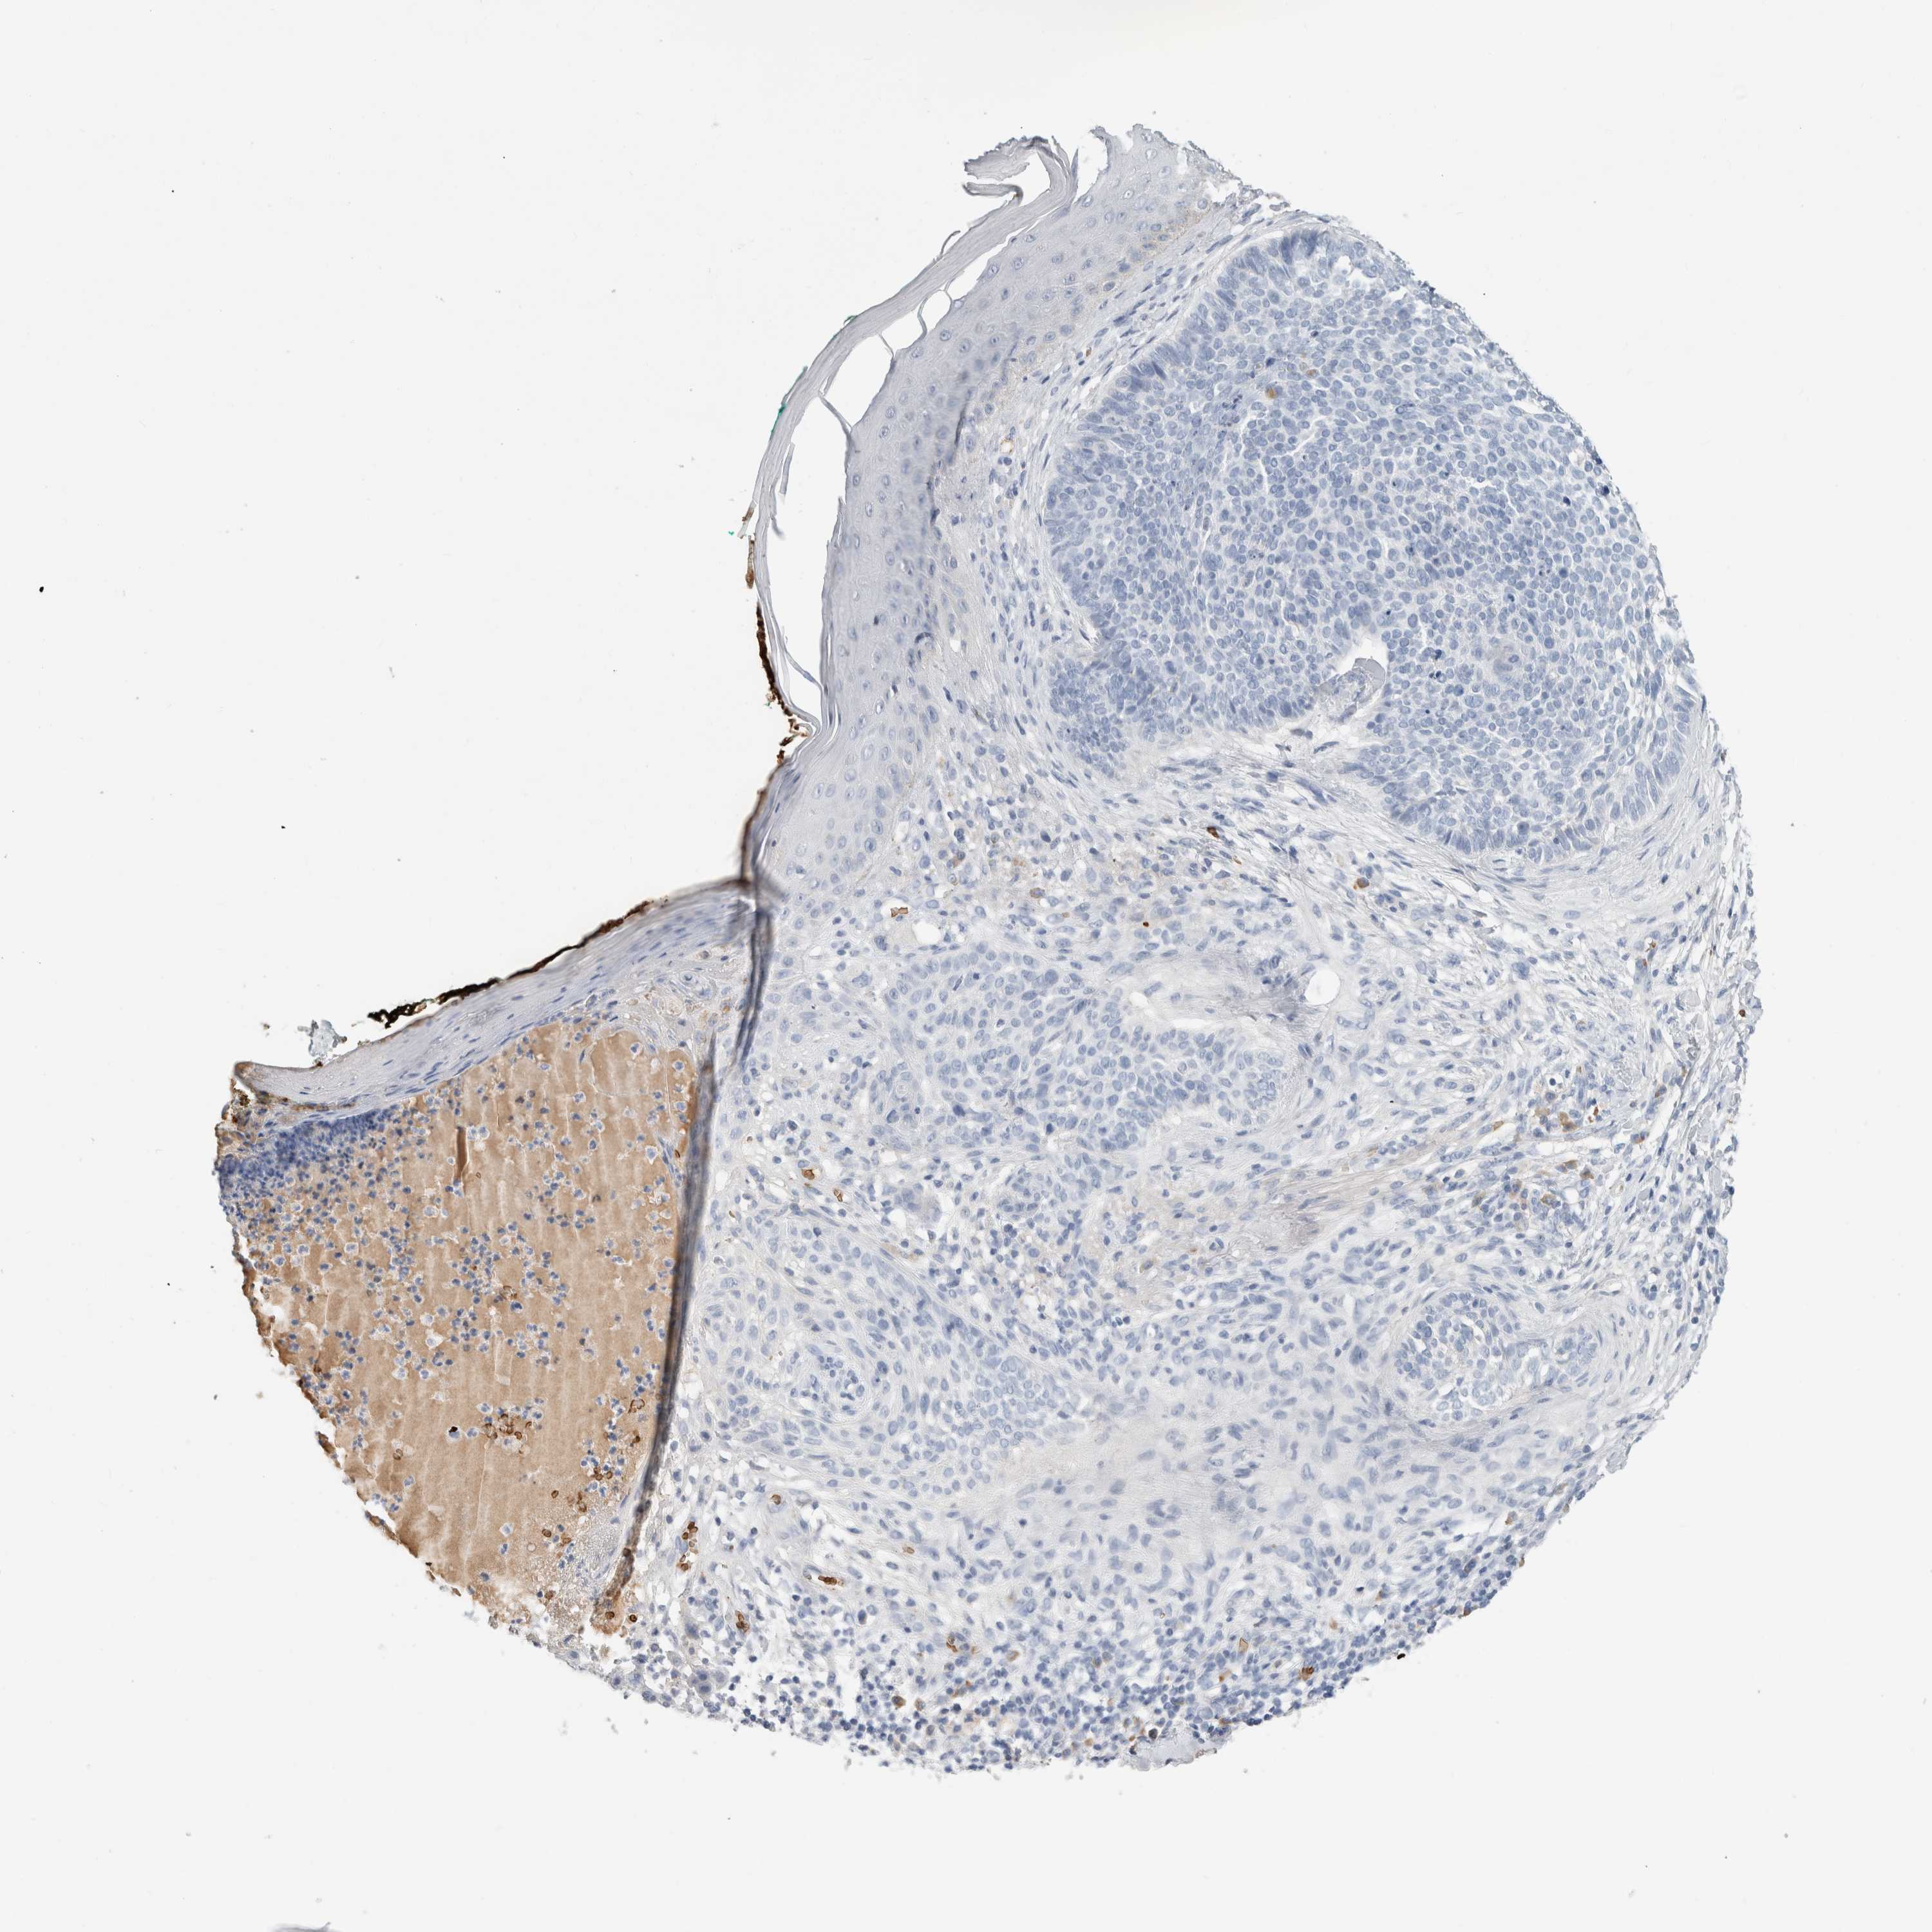

SKIN CANCER - Protein expressioni

A mouse-over function shows sample information and annotation data. Click on an image to view it in a full screen mode. Samples can be filtered based on level of antibody staining by selecting one or several of the following categories: high, medium, low and not detected. The assay and annotation is described here.

Antibody stainingi

Antibody staining in the annotated cell types in the current human tissue is reported as not detected, low, medium, or high, based on conventional immunohistochemistry profiling in selected tissues. This score is based on the combination of the staining intensity and fraction of stained cells.

Each image is clickable and will lead to virtual microscopy that enables deeper exploration of all samples and also displays staining intensity scores, fraction scores and subcellular localization as well as patient and tissue information for each sample.

Antibody HPA006558

Antibody CAB025790

Squamous cell carcinoma, NOS

Squamous cell carcinoma, metastatic, NOS

Basal cell carcinoma